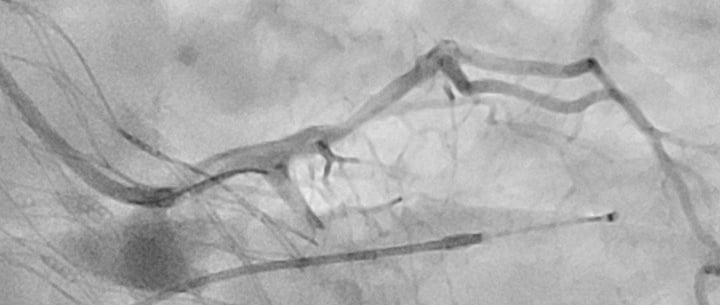

Nous avons développé une évaluation par guide FFR piégé pendant la procédure de TAVI, qui s'avère être une méthode sûre et simple d'utilisation dans le domaine de la cardiologie.